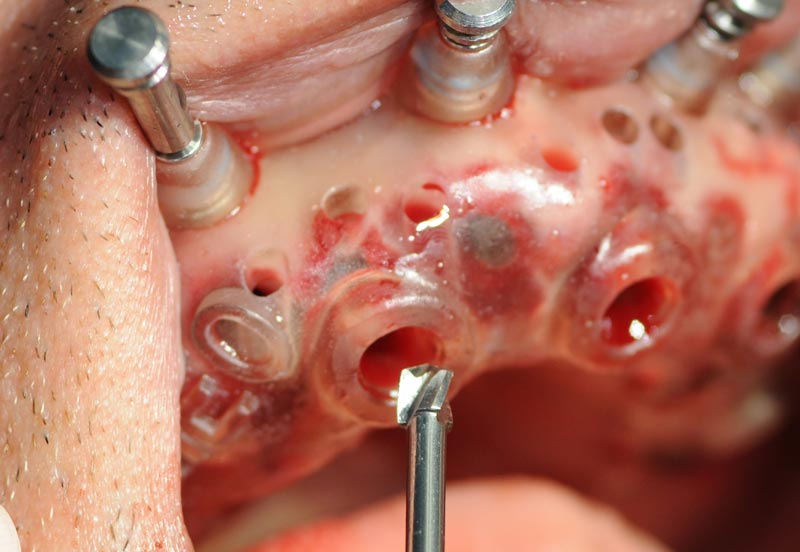

Fasi dell’intervento (Dott. Marano Giuseppe – Roma)